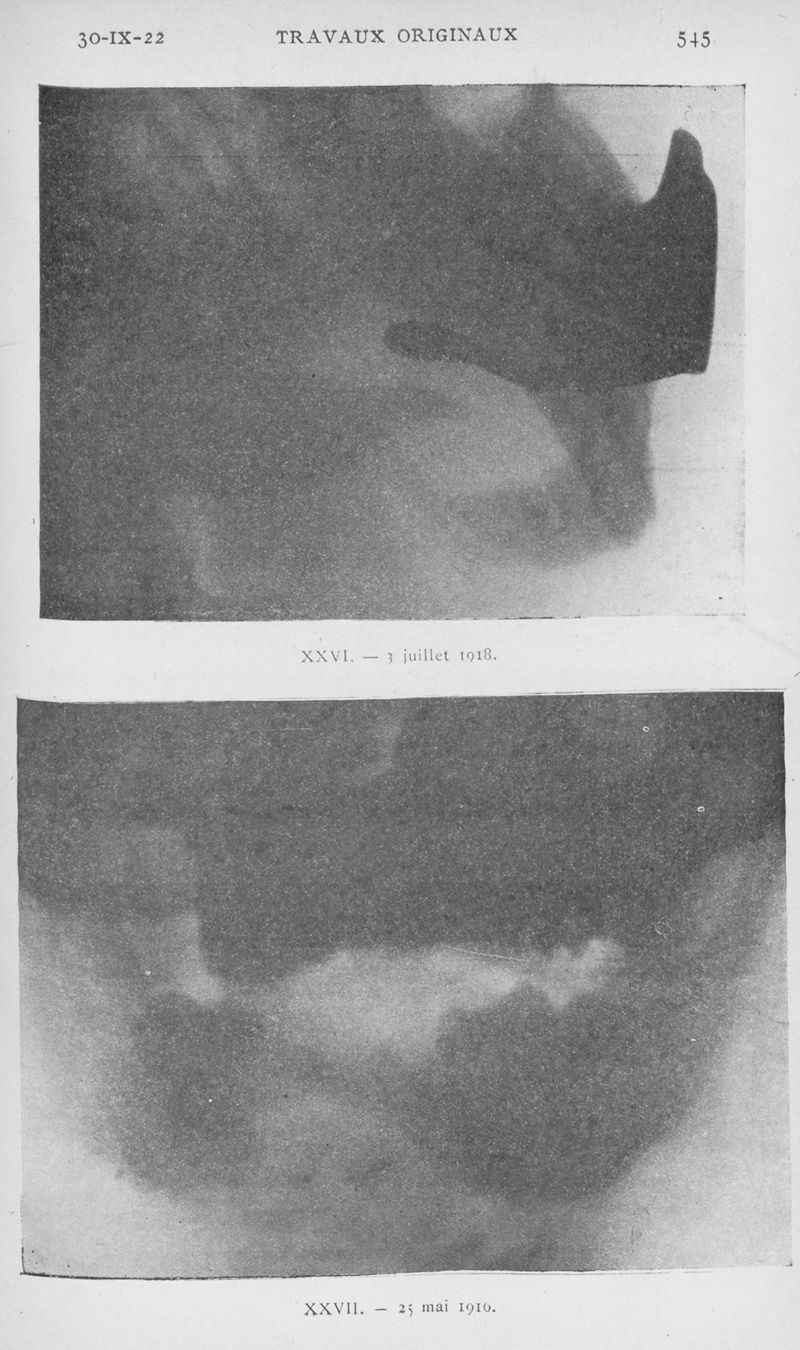

L'Odontologie

tome 60. - Paris, 1922.